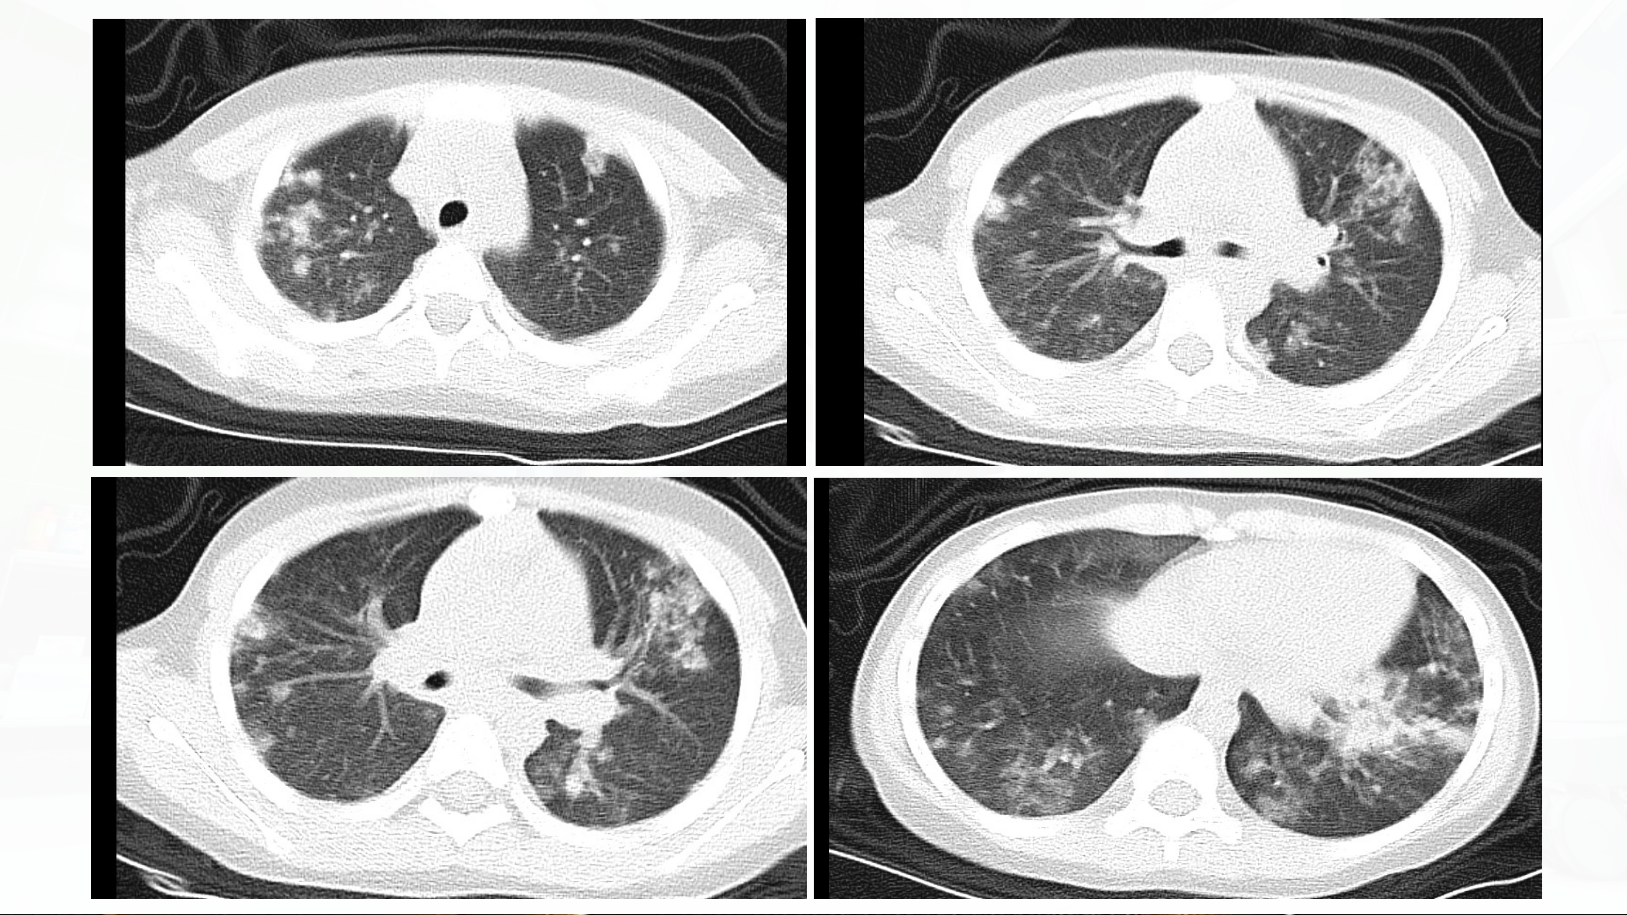

“肺炎”背后的真凶

2025儿科最佳临床实践华中科技大学同济医学院附属同济医院儿童感染消化科团队分享主讲嘉宾:马迪 主治医师点评嘉宾:周华 副主任医今日思考:发热、咳嗽、咯血、贫血,如何以一元论思维+多学科协作,梳理思路探寻病因?华中科技大学同济医学院附属同济医院儿童感染消化科是国家临床重点专科、华中科技大学“双一流”建设学科;是集医教研为一体的,具有突出优势的国内儿科医学高峰学科,一直引领我国儿科医学的发展。